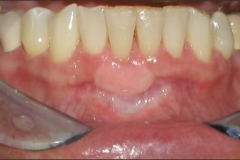

This patient experienced many areas of gum recession, primarily on the upper and lower front teeth. This patient's own tissue was used to correct the problem.

Click on a thumbnail to view the before and after photos.